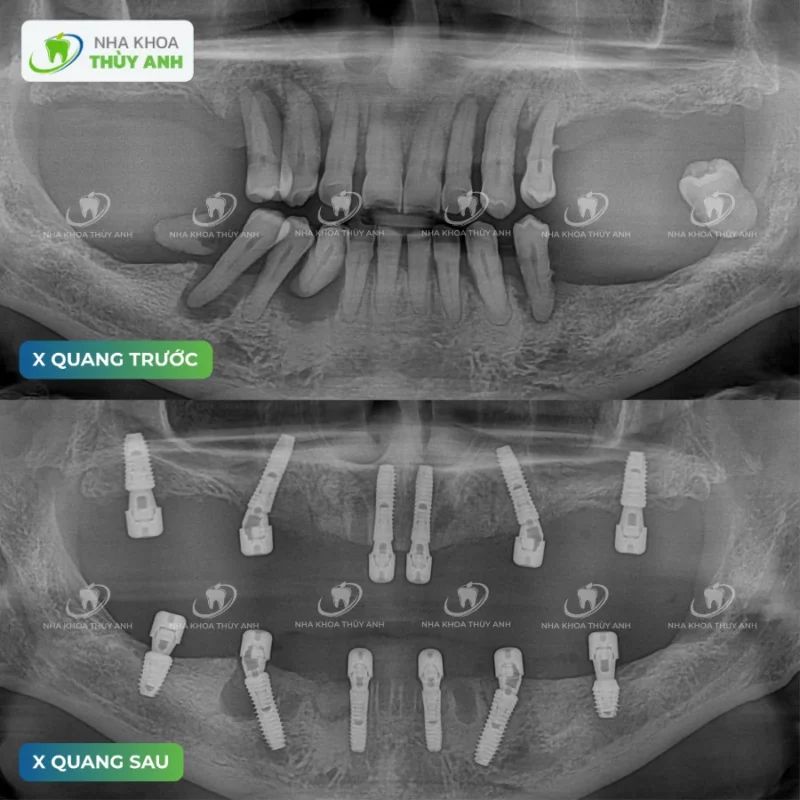

Trong buổi thăm khám đầu tiên, tình trạng răng miệng của ông đã ở mức khá nghiêm trọng. Gần như toàn bộ răng hàm đã mất, những chiếc răng còn lại bị viêm nha chu nặng, lung lay và không còn khả năng giữ lại. Khả năng ăn nhai suy giảm rõ rệt, việc ăn uống mỗi ngày trở thành một áp lực thay vì là một niềm vui.

Sau khi thăm khám và hội chẩn, bác sĩ đưa ra phương án điều trị phù hợp nhất: loại bỏ toàn bộ những răng không còn khả năng giữ lại và cấy 6 trụ implant cho mỗi hàm để phục hình toàn hàm cố định.

Đây là một kế hoạch điều trị lớn, nhưng cần thiết để giúp ông có thể ăn nhai ổn định và lâu dài về sau. Toàn bộ quá trình được chuẩn bị rất kỹ lưỡng, từ việc kiểm tra xương hàm, lên kế hoạch đặt trụ đến từng bước thực hiện. Mọi thứ đều có lộ trình rõ ràng, giúp ông hiểu mình đang trải qua điều gì và sẽ đạt được kết quả ra sao. Dù là một ca điều trị phức tạp, nhưng cách làm việc bài bản và chắc chắn khiến ông yên tâm hơn rất nhiều.